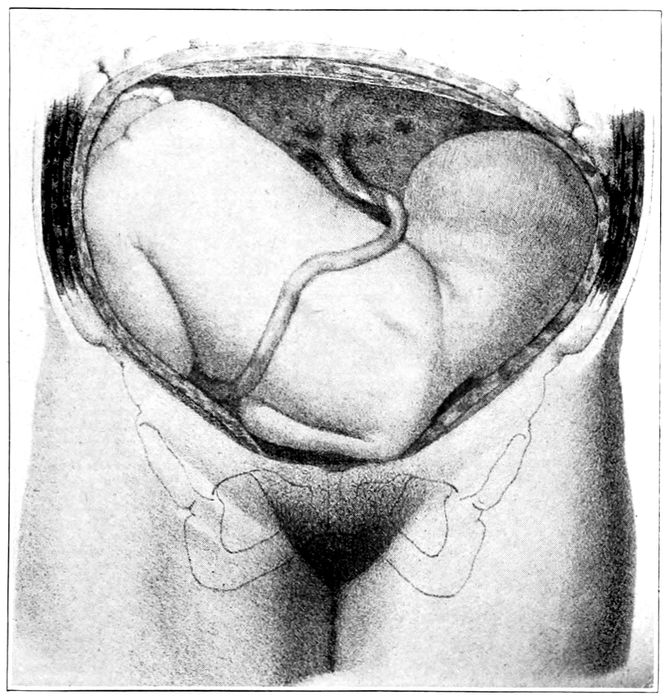

Fig. 19.—The egg at term with uterus removed and child showing through the membranes. (Edgar.)